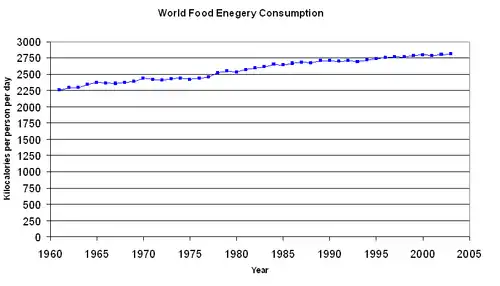

Excess appetite for palatable, high-calorie food (especially fat, sugar, and certain animal proteins) is seen as the primary factor driving obesity worldwide, likely because of imbalances in neurotransmitters affecting the drive to eat,[108] as well as changes to the duodenum impacting nutrient sensing and signaling. Dietary energy supply (the amount of calories in available food) per capita varies markedly between different regions and countries. It has also changed significantly over time.[107] From the early 1970s to the late 1990s the average food energy available per person per day (the amount of food bought) increased in all parts of the world except Eastern Europe. The United States had the highest availability with 3,654 calories (15,290 kJ) per person in 1996.[107] This increased further in 2003 to 3,754 calories (15,710 kJ).[107] During the late 1990s, Europeans had 3,394 calories (14,200 kJ) per person, in the developing areas of Asia there were 2,648 calories (11,080 kJ) per person, and in sub-Saharan Africa people had 2,176 calories (9,100 kJ) per person.[107][109] Total food energy consumption has been found to be related to obesity.[110]

The widespread availability of dietary guidelines[111] has done little to address the problems of overeating and poor dietary choice.[112] From 1971 to 2000, obesity rates in the United States increased from 14.5% to 30.9%.[113] During the same period, an increase occurred in the average amount of food energy consumed. For women, the average increase was 335 calories (1,400 kJ) per day (1,542 calories (6,450 kJ) in 1971 and 1,877 calories (7,850 kJ) in 2004), while for men the average increase was 168 calories (700 kJ) per day (2,450 calories (10,300 kJ) in 1971 and 2,618 calories (10,950 kJ) in 2004). Most of this extra food energy came from an increase in carbohydrate consumption rather than fat consumption.[114] The primary sources of these extra carbohydrates are sweetened beverages, which now account for almost 25 percent of daily food energy in young adults in America,[115] and potato chips.[116] Consumption of sweetened beverages such as soft drinks, fruit drinks, and iced tea is believed to be contributing to the rising rates of obesity[117][118] and to an increased risk of metabolic syndrome and type 2 diabetes.[119] Vitamin D deficiency is related to diseases associated with obesity.[120]